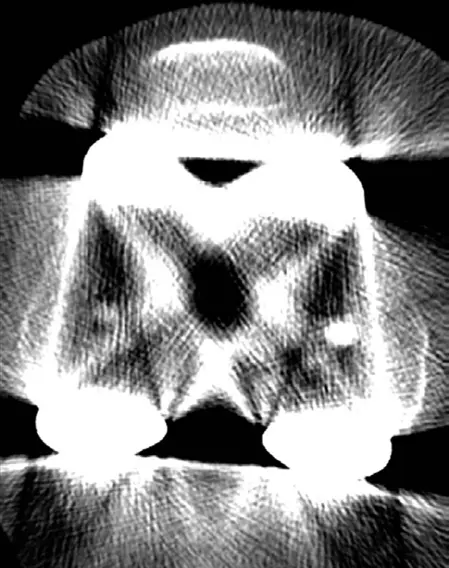

دراسات التصوير

تُعد دراسات التصوير ضرورية لتأكيد التشخيص وتحديد نوع ودرجة سوء المحاذاة بدقة.

-

الأشعة السينية (X-rays):

- المنظر الأمامي الخلفي (AP View) والجانبي (Lateral View) للركبة: تُستخدم كفحص أولي لتقييم وضع المكونات بشكل عام، وحجمها، والبحث عن أي علامات ارتخاء أو كسر.

- منظر ميرشانت (Merchant View) للرضفة: يُركز على الرضفة والميزاب الفخذي لتقييم تتبع الرضفة وميلانها.

- الأشعة السينية الواقفة لكامل الطرف السفلي (Full-Length Standing AP Radiograph / Long Leg Alignment View): تُعتبر "المعيار الذهبي" لتقييم المحور الميكانيكي الكلي للطرف السفلي. تسمح هذه الصورة بقياس الخط الواصل من مركز رأس الفخذ إلى مركز الكاحل، مروراً بالركبة، مما يوفر تقييماً شاملاً للمحاذاة الإكليلية وتوزيع الحمل.

- التصوير المقطعي المحوسب (CT Scan):